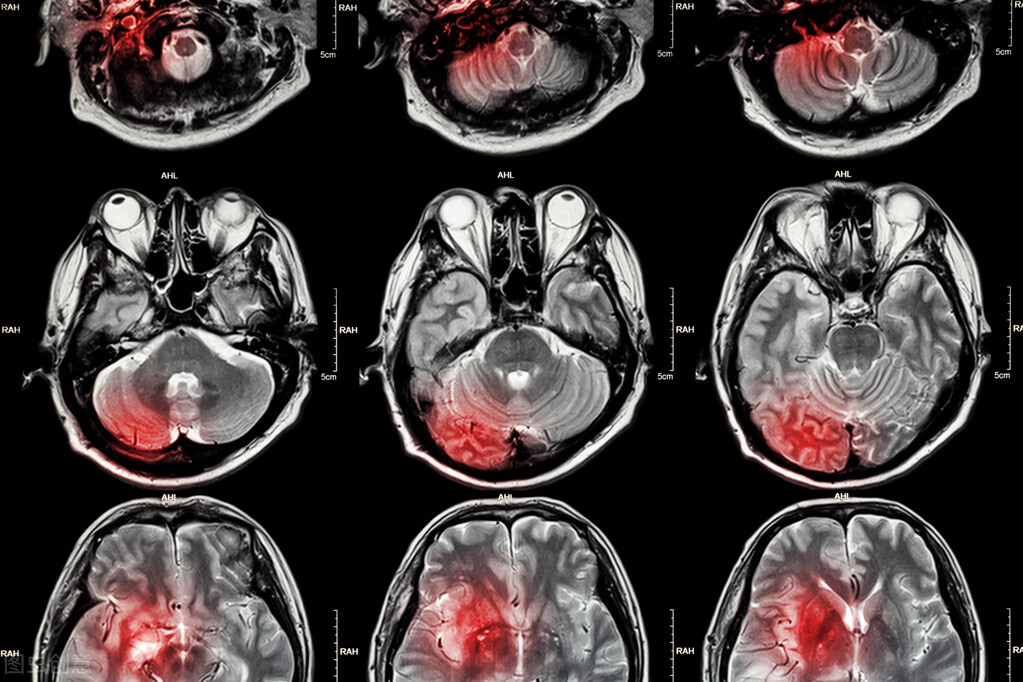

随着颈动脉狭窄程度的加深,脑部的缺氧症状也会更加明显。这个时候患者可能会出现 脑部缺氧的症状 ,比如 头晕、肢体麻木、眼前发黑、一过性的失语和瘫痪等,严重的时候患者会出现持续性的脑缺血的症状(具体如上)。

很多人的颈动脉斑块是比较软的,这种斑块是不结实的, 当人在情绪激动、暴饮暴食、高脂饮食、血压升高等情况的时候,这个斑块就有可能会脱落,随着血流进入脑部,从而引发脑梗死。

脑梗死的严重性不言而喻,很多人即便能保住一条命,但是其后遗症也是会严重影响生活质量的。 很多脑梗死患者出院后不能说话、不能行走,完全丧失了生活自理能力,这个时候需要专门有人照顾,这无疑会增加家庭和社会的负担。